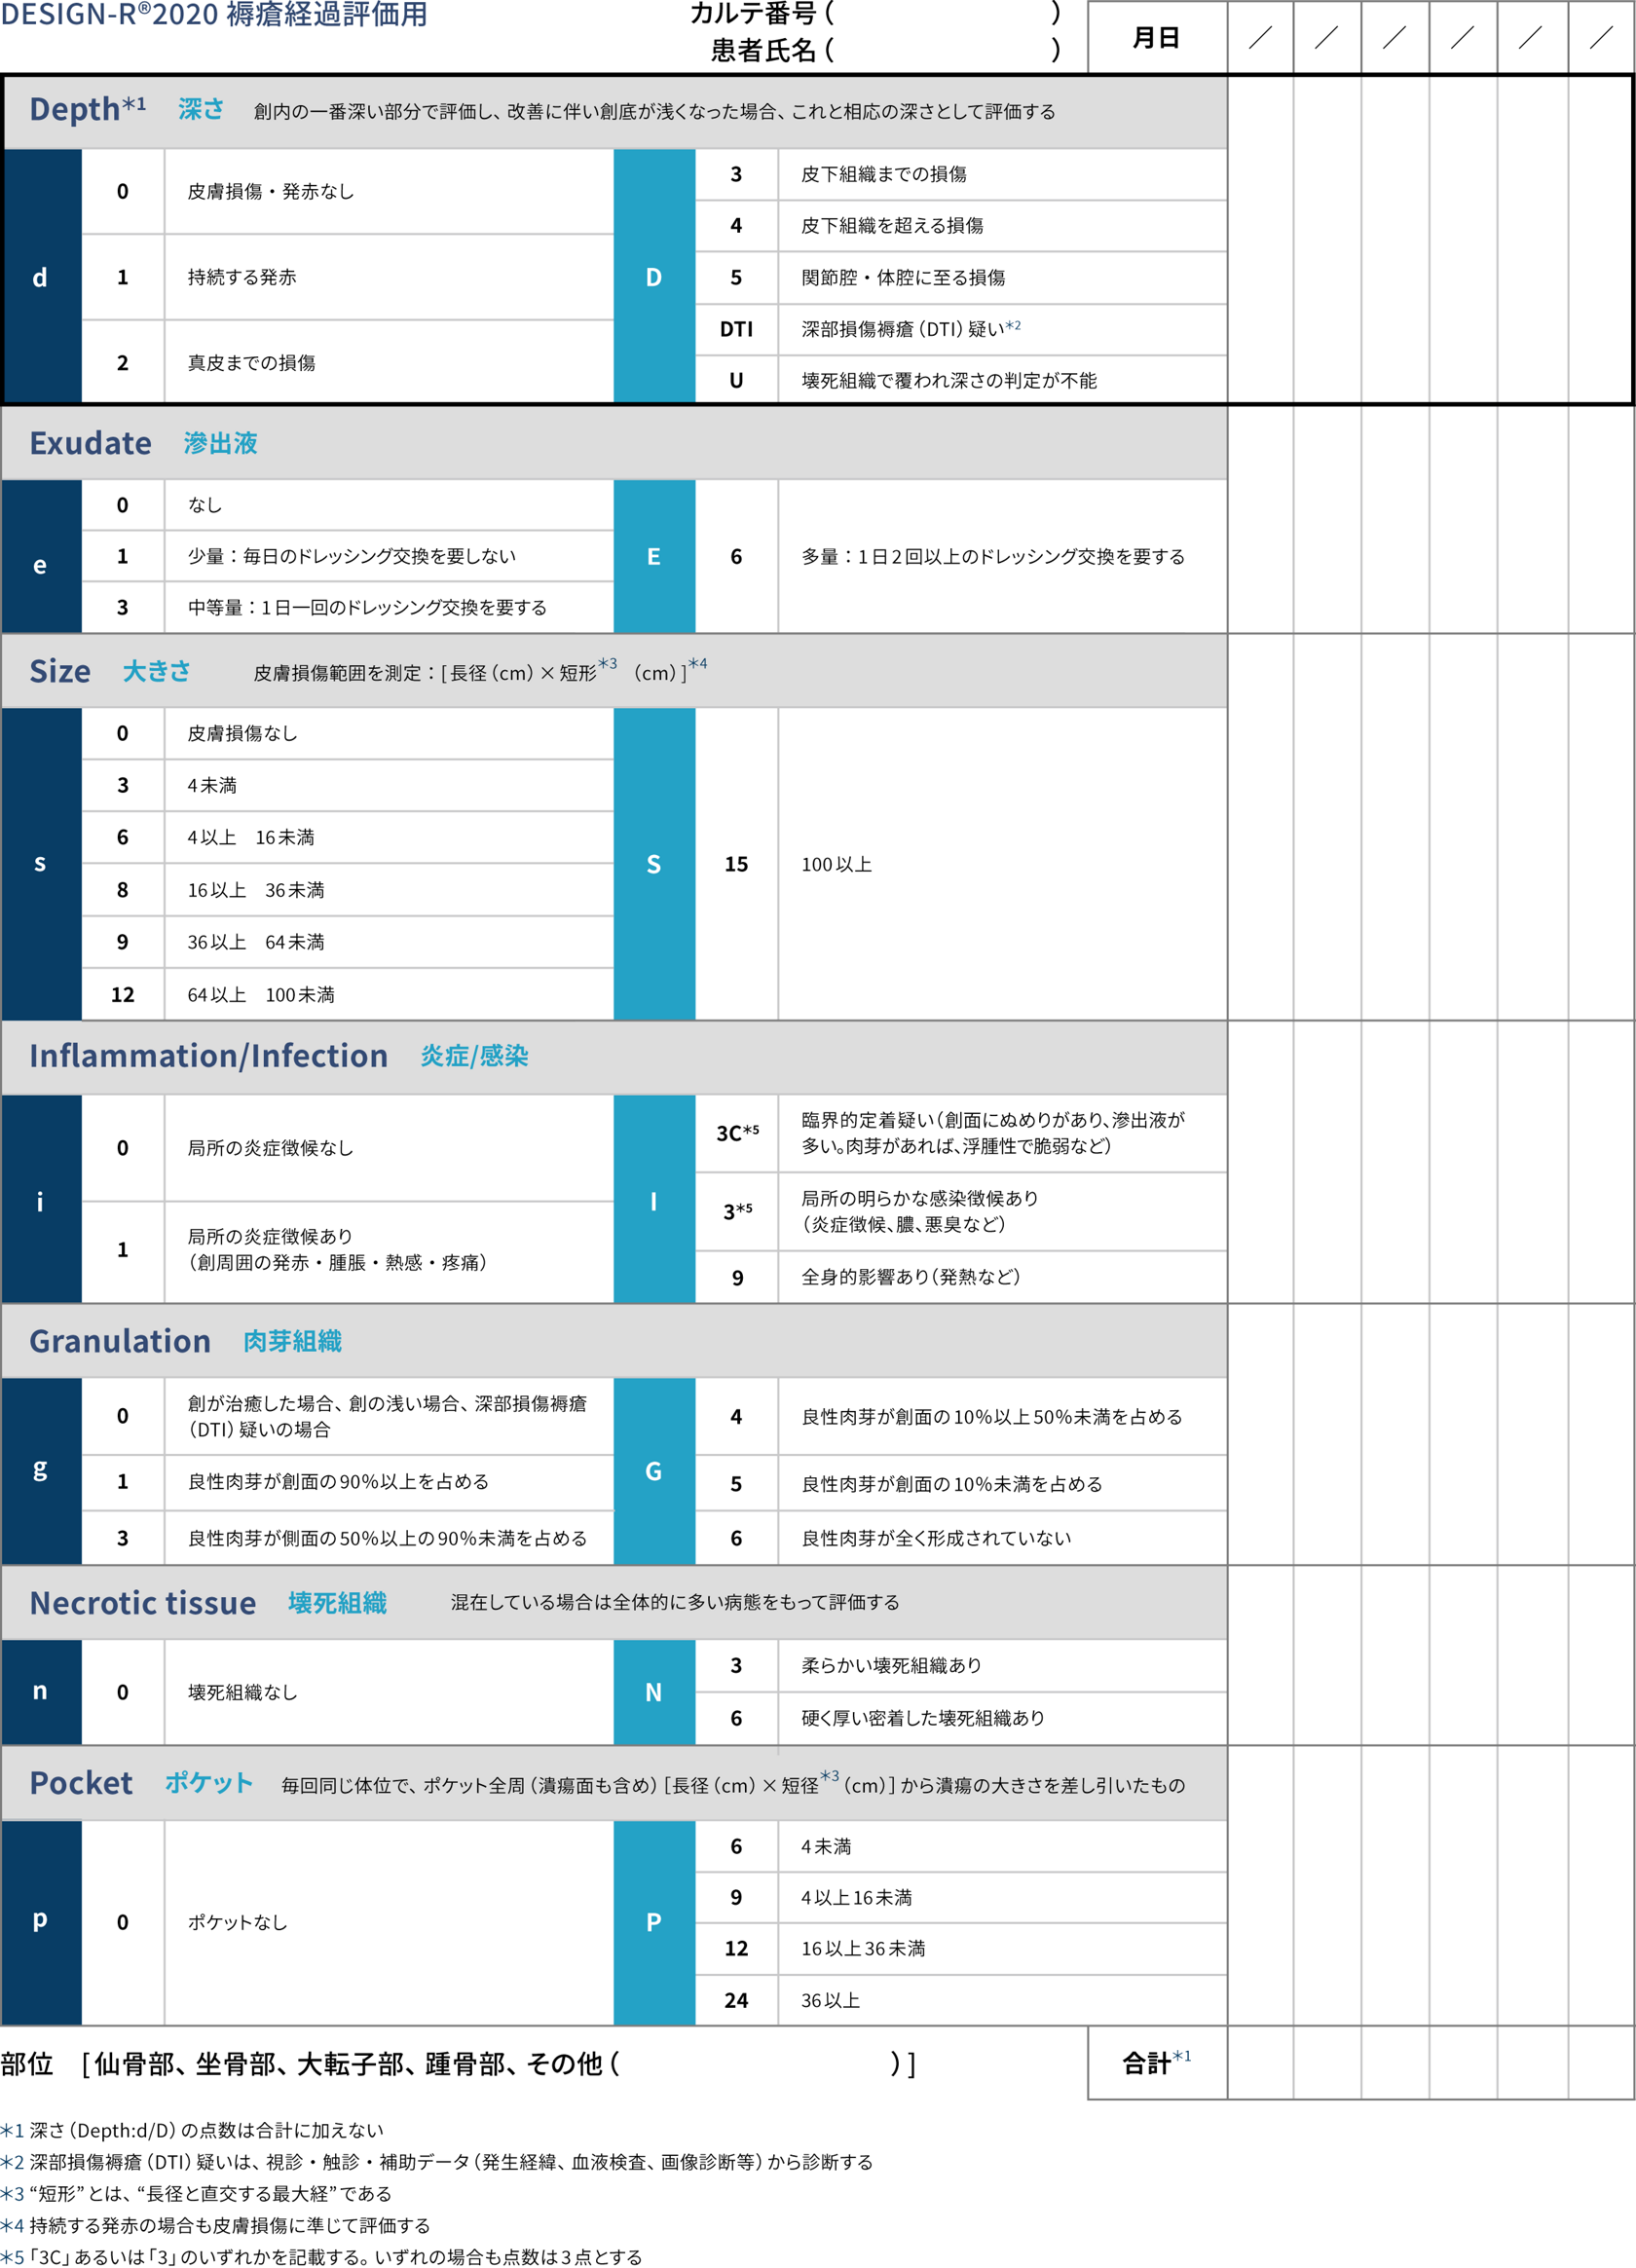

看護師のための褥瘡評価の完全ガイドDESIGN-R評価 - しごとレトリバーガイド。

特集2 DESIGN-R®2020について花王ハイジーンソルーション。

特集2 DESIGN-R®2020について花王ハイジーンソルーション。

特集2 DESIGN-R®2020について花王ハイジーンソルーション。

特集2 DESIGN-R®2020について花王ハイジーンソルーション。

褥瘡の評価 DESIGN-R デザインアール を用いた評価のコツナース専科。

褥瘡評価スケールの種類とDESIGN-R®2020による評価方法 医療従事者対象ネスレ栄養ネット。

褥瘡の評価 DESIGN-R デザインアール を用いた評価のコツナース専科。

看護師のための褥瘡評価の完全ガイドDESIGN-R評価 - しごとレトリバーガイド。